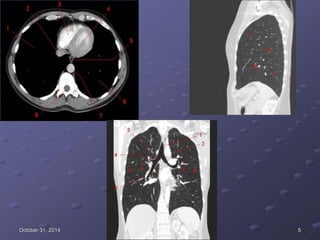

October 31, 2014 4

October 31, 2014 5